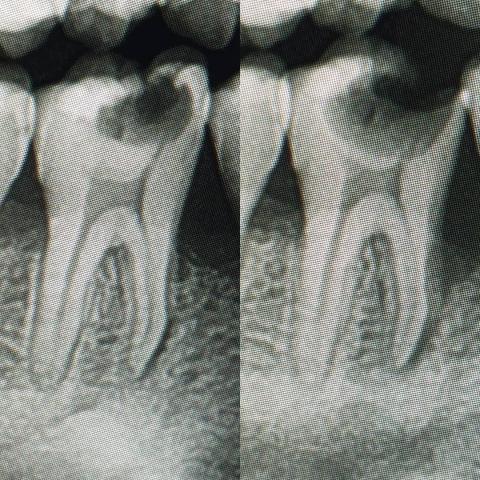

Case Type: Advanced Dental Caries and Calculus Accumulation

Upon examination, the posterior molars exhibit:

Extensive caries (tooth decay) on both left and right sides.

Possible pulp involvement — dark discoloration and cavity penetration indicate the decay may have reached the pulp chamber.